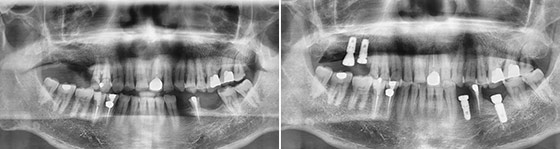

任博士术前通过三维CT扫描,测出患者缺牙部位牙槽骨的高度、宽度、密度,提前预定种植的位置、角度、深度。数字化导板技术,全程导航,完成2颗种植体的植牙手术仅用5分钟,手术全程精准、舒适,手术效果震撼全场。